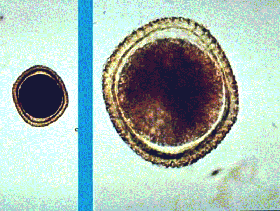

Distocide 600 mg thuộc nhóm dược lý thuốc trị ký sinh trùng, chống nhiễm khuẩn, ngoài biệt dược này còn có một số loại biệt dược khác đang sử dụng tại các quốc gia trên thế giới như Prazintel, Biltricid, Cysticid, Droncit, Cesol,…dạng đóng gói là viên nénbao phim, thành phần chính của thuốc là praziquantel, dẫn xuất pyrazino-isoquinolein. Thuốc praziquantel được sán hấp thu nhanh, tăng tính thẩm thấu của màng tế bào, dẫn tới mất calci nội bào, làm co cứng và liệt hệ cơ của sán nhanh chóng; đồng thời da của sán trưởng thành xuất hiện các mụn nước rồi sau đó bị vỡ tung và phân hủy.